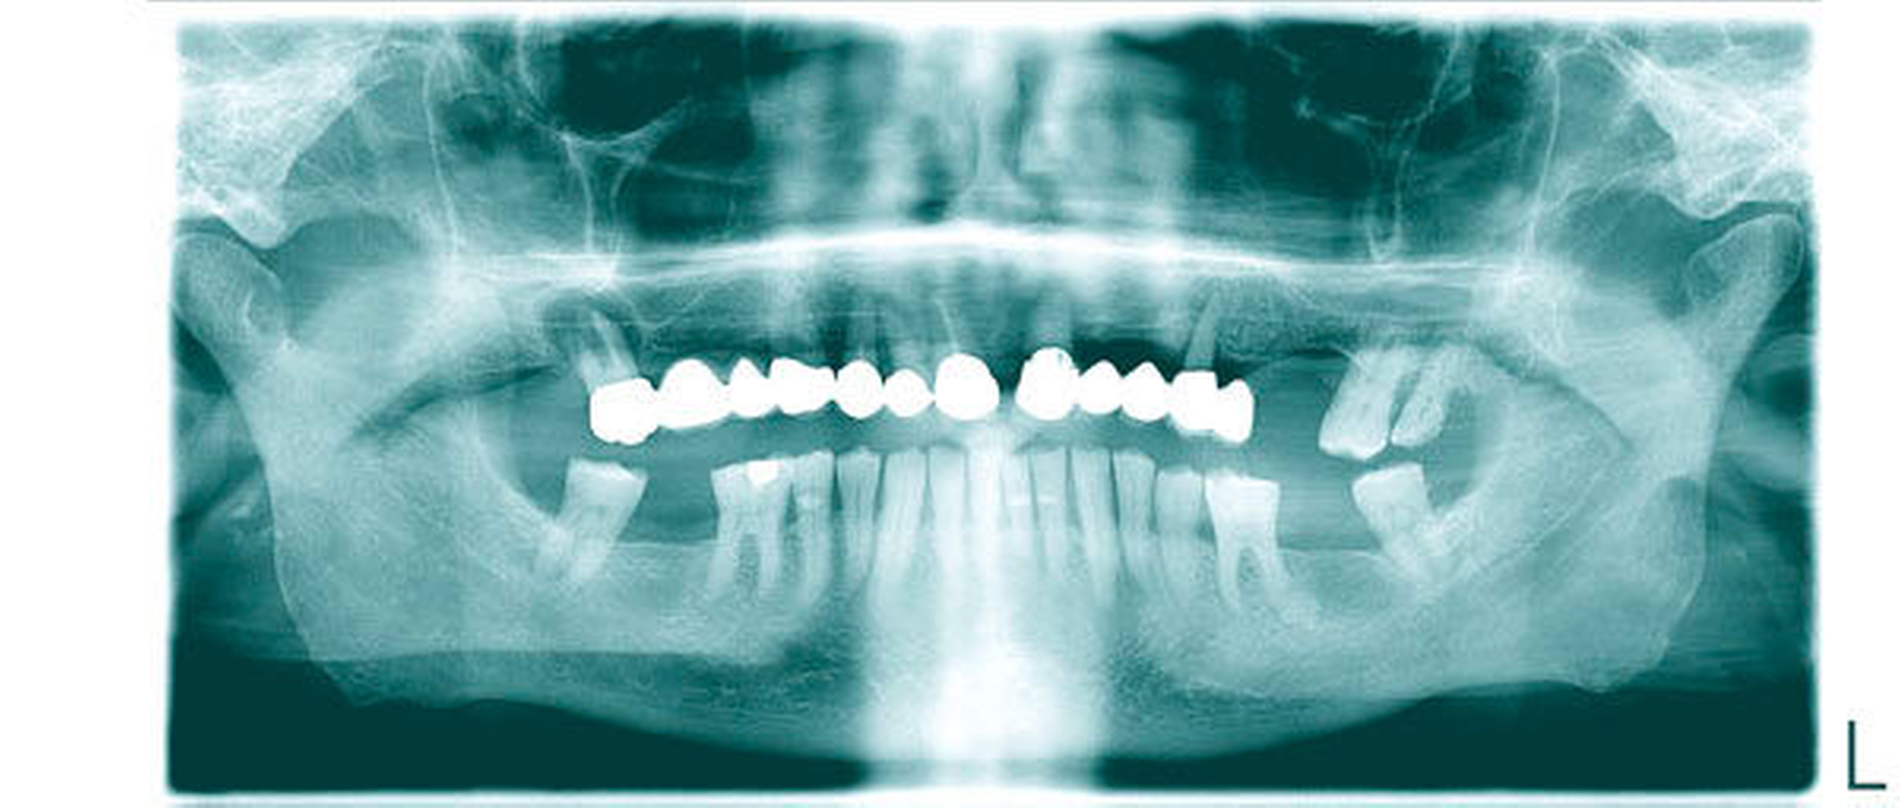

Systemische Erkrankungen mit Auswirkungen auf die oralen und perioralen Gewebe sowie die eng damit im Zusammenhang stehende Einschränkung der Lebensqualität wie Hyposalivation beziehungsweise Xerostomie (zum Beispiel bei Morbus Sjögren oder als unerwünschte Arzneimittelwirkung), Einschränkung der Mundöffnung und Kaufunktion (zum Beispiel bei rheumatischen Erkrankungen des Kiefergelenks, bei systemischer Sklerose, Fibromyalgie), Schmerzen, Missempfindungen, entzündlichen – teils aphthoiden – Läsionen der Mundschleimhaut (zum Beispiel bei systemischem Lupus erythematodes, Wegenerscher Granulomatose, Fibromyalgie, Riesenzellarteriitis) oder auch Einschränkungen der Immunabwehr mit gesteigertem Infektions- oder Blutungsrisiko (zum Beispiel beim systemischen Lupus erythematodes durch Leukozytopenie, Lymphozytopenie oder Thrombozytopenie) können oft die Verläufe von Wundheilungsvorgängen nach oralchirurgischen Interventionen negativ beeinflussen. Andererseits kann es auch durch unerwünschte Arzneimittelwirkungen im Zusammenhang mit der Behandlung dieser Erkrankungen (zum Beispiel beim Einsatz von Immunsuppressiva) zu Störungen der Wundheilungsverläufe kommen. Ein typisches Beispiel im oralchirurgischen Praxisalltag zeigen Abbildung 1 und Tabelle 2. Eine 72-jährige multimorbide Patientin nimmt 13 Pharmaka über 19 Einzeldosen pro Tag und einmal halbjährlich ein Medikament ein. Therapiewunsch dieser Patientin ist eine Implantat-vermittelte Rehabilitation des Oberkiefers nach indizierter Extraktionstherapie.